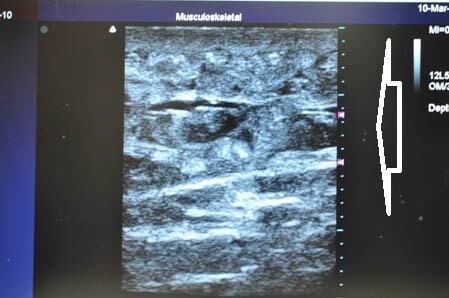

上記の画像の部分をつまんでみましょう。

↓ ↓ ↓

同様に下腹部も見ておきましょう。